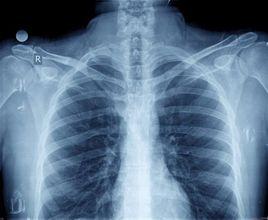

老年人吸入性肺炎的臨床表現無特異性。常有低熱,咳嗽或乾咳無力,痰不易咯出,痰中常含多種細菌。臥床患者常侵犯肺上葉後段和下葉尖段。坐位患者常累及兩肺底部。